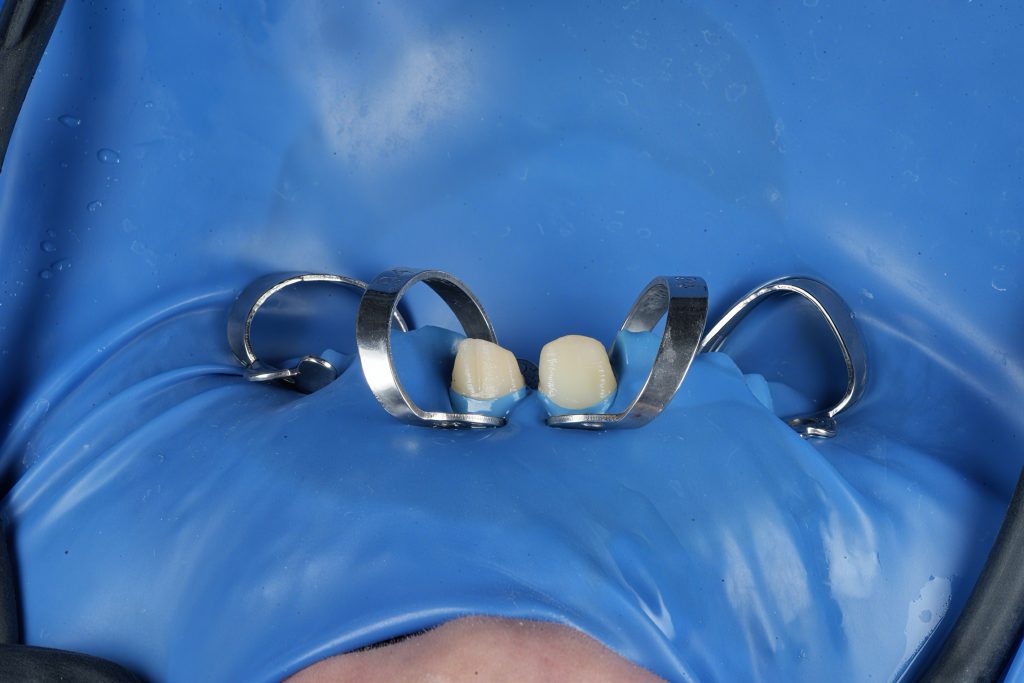

Rubber-dam isolation (blue dam) was secured using W2A clamps for moisture control and soft-tissue protection (Fig 1-2).

Conservative access cavities were prepared under dental microscope to preserve marginal ridges and optimize canal entry (Fig 5-7).